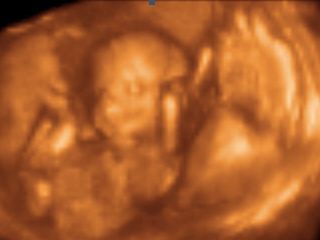

Ahojcek babulky trosku sa Vam sem vtirknem ...mam otazocku neviete kolky den po PK by mohlo byt uhniezdenie ? dakujem velmi pekne